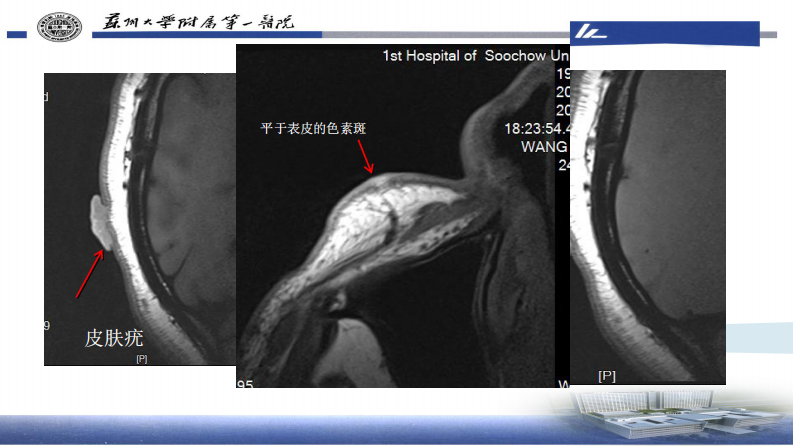

皮肤肿瘤HRMRI成像—李勇刚.pdf